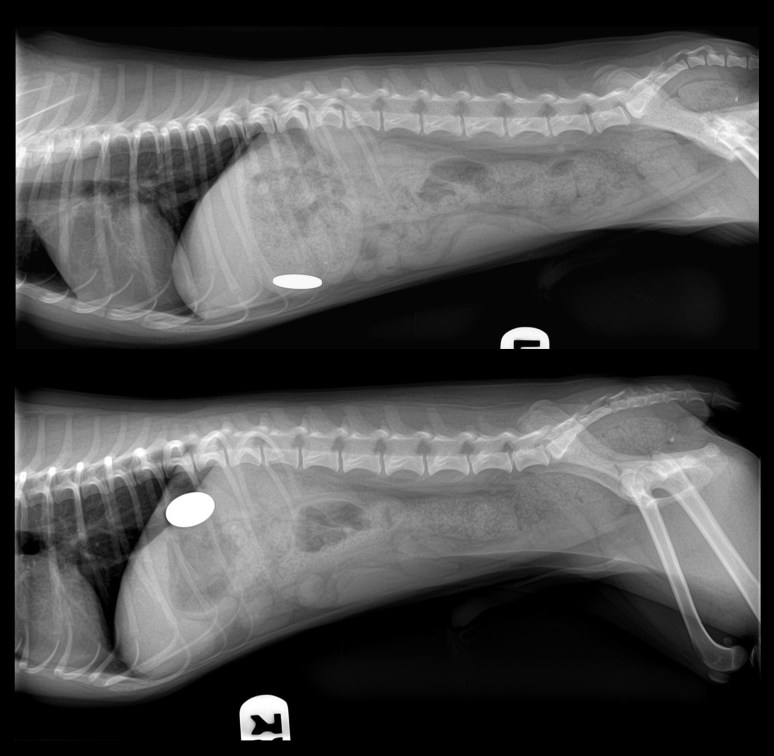

De combien seriez-vous plus riches après avoir retiré la pièce de monnaie qui est dans l’estomac de ce chien ?